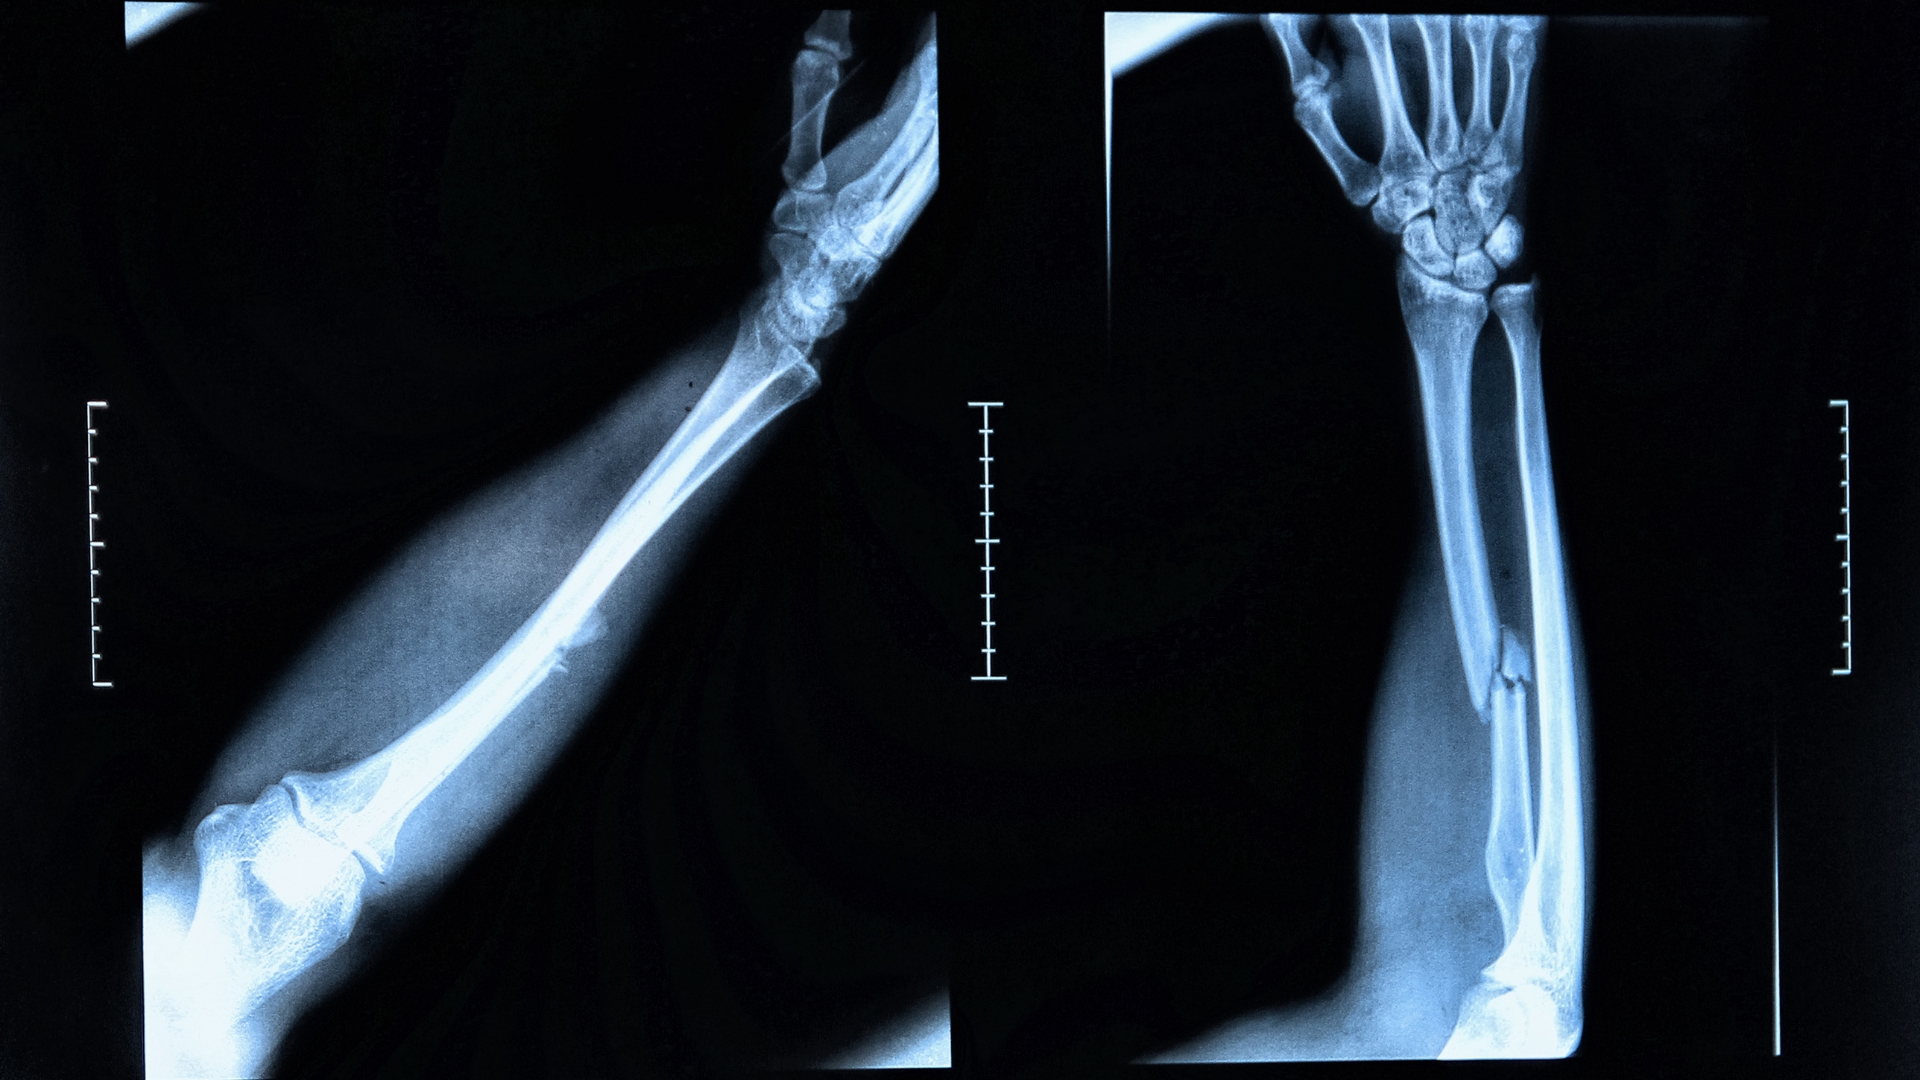

X-quang xương cẳng tay là phương pháp chẩn đoán hình ảnh sử dụng tia X để tạo ra hình ảnh của hai xương chính ở cẳng tay là xương quay và xương trụ. Hình ảnh thu được giúp bác sĩ quan sát cấu trúc xương, phát hiện đường nứt, gãy, biến dạng hoặc những thay đổi bất thường liên quan đến khớp cổ tay và khuỷu tay.

Trong thực tế, người bệnh thường được chụp ở ít nhất hai tư thế cơ bản gồm tư thế thẳng và tư thế nghiêng. Việc chụp ở hai góc khác nhau giúp đánh giá toàn diện trục xương và mức độ di lệch nếu có. Nhờ đó, các tổn thương nhỏ hoặc gãy kín khó nhận thấy trên một mặt phẳng duy nhất sẽ ít bị bỏ sót hơn.

Tư thế thẳng: Cẳng tay được duỗi thẳng hoàn toàn, lòng bàn tay ngửa và đặt sát mặt bàn chụp. Tư thế này giúp quan sát toàn bộ chiều dài xương quay và xương trụ.

Tư thế nghiêng: Cẳng tay xoay sang một bên, cạnh ngoài áp sát bàn để đánh giá sự di lệch theo chiều trước - sau.